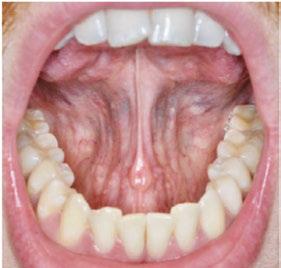

tan was referred to my office by a TMD specialist. His chief complaints were he could not chew or open his mouth without pain. It seemed the less he chewed, the more pain he experienced. As a result, an Orofacial Myofunctional Therapy (OMT) program was created to help support his muscles of the TMJ and craniofacial respiratory complex. He used his splint as instructed by his specialist. However, his anterior open bite widened, and his teeth became more misaligned over time.

Stan was a 28-year-old male in a lot of pain. He had just come from his TMJ specialist where he received an oral orthotic splint to relieve his discomfort. He told me it all started after a long dental appointment where he received a root canal and a new crown on the upper right. After this procedure, his jaws felt tight so he gave it a good stretch by opening very wide. He heard a rip and a crunch. Opening his mouth was never the same after that. He presented with a set of symptoms: TMD muscle pain, he could no longer chew his food without pain (food had to be the soft consistency of tofu), daytime clenching and night time grinding of his teeth. In addition, he had daily headaches and ear ringing. He could not open his mouth very wide without experiencing sharp pain. He took acetaminophen for his discomfort and zolpidem nightly to help him fall asleep easier.

Upon closer examination, there were contributing factors that led to his discomfort. Stan had been a stomach/face sleeper for years. He also bit his nails since childhood, had a smoking habit from his youth, and he was prone to ear infections. He had moderate tongue and buccal ties, obligate mouth breathing, aggravated by a deviated septum, narrow nares, low tongue resting posture, an

anterior open bite, a lower jaw that deviated upon opening, and bouts of acid reflux.

An orofacial therapy program was created to allow his tongue to give better support and function to his oral structures, especially the TMJ joint. When the tongue naturally rests in the palate, it removes the unwanted pressure off of the TMJ. As part of the course of his therapy, focus was made to reeducate his breathing to make his nose the primary way he breathes. Optimal breathing rate for an adult is slower than for a child. Good nasal breathing during the day supports good nasal breathing during the night for optimal sleep. When the tongue rests in the palate, it impacts facial development especially for children who are still growing. An adult, for example, like our friend Stan, the progress made is gradual but more likely to last a lifetime. Generally, therapy starts out once a week for about 2-3 months. Then therapy progresses to every other week for 2-3 months, and then changes to once a month for about 5 months for the rest of the year. The exercises are done a minimum of 2 times everyday. These exercises are designed to strengthen and tone the orofacial muscles, building brand new neuromuscular function. When the muscles of the face are well developed, it may favorably impact appearance and the overall integrity of the facial structures. The muscles of the face also include the tongue, lips, cheeks and neck. Although the therapy program is typically only a year, Stan really liked how good he felt and decided to continue with some of the exercises to this day. From the photos you can see how much the program has impacted his health and well-being.

During his therapy, there was a discussion about the possible benefits he may receive from having his jaws expanded, making more room for his tongue, then to be followed by a tongue and buccal frenums release. His intermolar width is 34 mm, and his intercanine width is 25 mm. I feel any expansion has a potential benefit.

Stan has a very narrow external nasal valve and receives some benefit from using dilator nasal strips. There are a few more products on the market that may help make

nasal breathing easier for him.

To document any initial assessment, the midpoint of therapy, and when therapy has ended, it is important to take detailed photos, videos, plus full measurements of the face and teeth. This makes it possible to compare results while showing that your therapy works based on the evidence you gathered before, during, and after treatment.